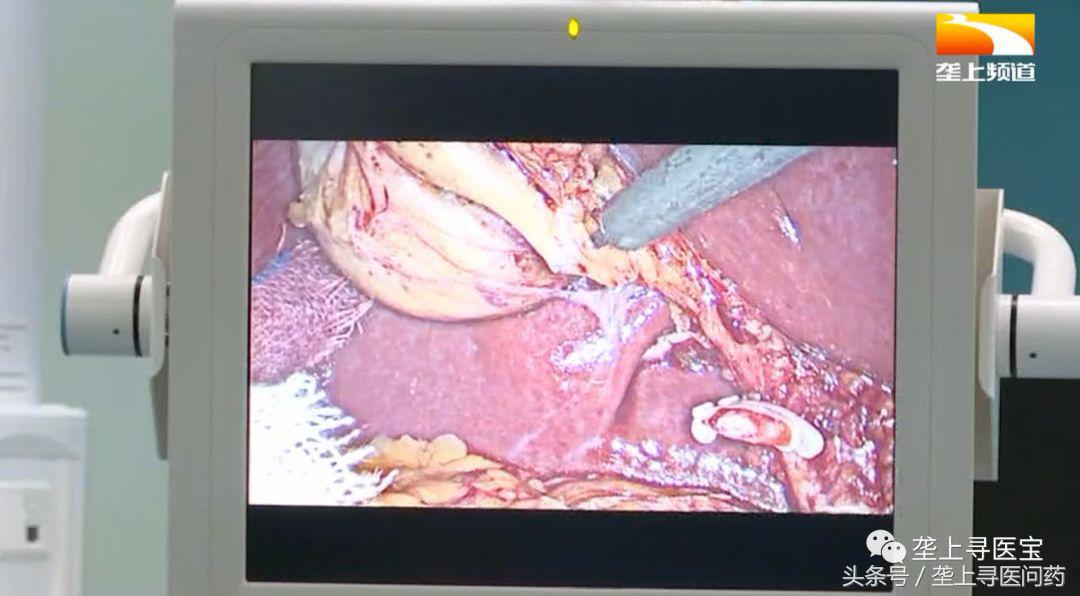

首先主刀医生要在患者脐部做第一个切口插入套管,腹腔内充入二氧化碳建立气腹,探查腹腔后,主刀医生找到了患者的病灶处,也就是胆囊,然后正式开始切除工作。

主刀医生先后夹闭胆囊管和胆囊动脉并完成与肝脏的游离解剖。

最后,医生成功将切除的胆囊从患者的腹腔取出。

手术直播图集